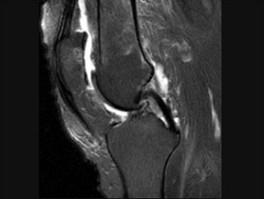

髌骨软骨软化症(如图)的治疗原则哪项是错误的 ( )A、非甾体类抗炎药B、一旦发现尽可能早手术治疗C、物理治疗D、关节内封闭 ...

问题 髌骨软骨软化症(如图)的治疗原则哪项是错误的 ( )

选项 A、非甾体类抗炎药 B、一旦发现尽可能早手术治疗 C、物理治疗 D、关节内封闭 E、股四头肌锻炼

答案 B